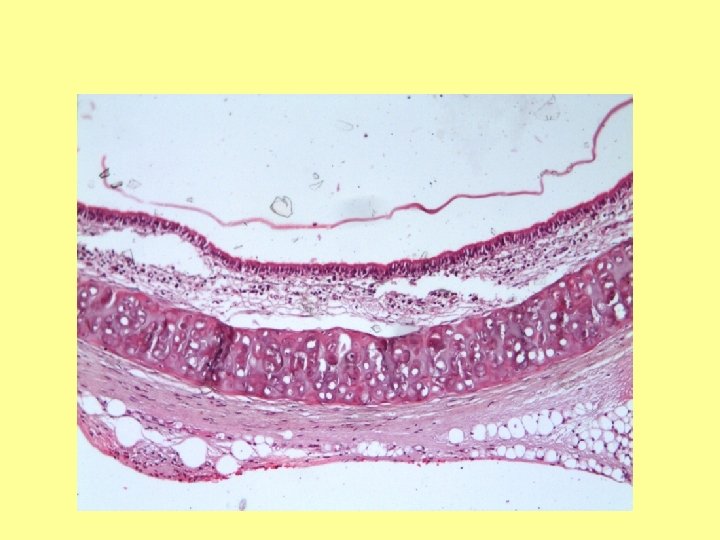

Yalancı Çok Katlı Kinosilyalı Epitel Preparat: Trakea-Özefagus (39) Kesit: Enine Boya: Hematoksilen-Eozin Lümen Özefagus

Yalancı Çok Katlı Kinosilyalı Epitel Preparat: Trakea-Özefagus (39) Kesit: Enine Boya: Hematoksilen-Eozin Lümen Özefagus Trakea Genel Görüntü (4 X 10)

Yalancı Çok Katlı Kinosilyolu Epitel Bazal Membran

Kinosilyum Yalancı Çok Katlı Kinosilyalı Epitel